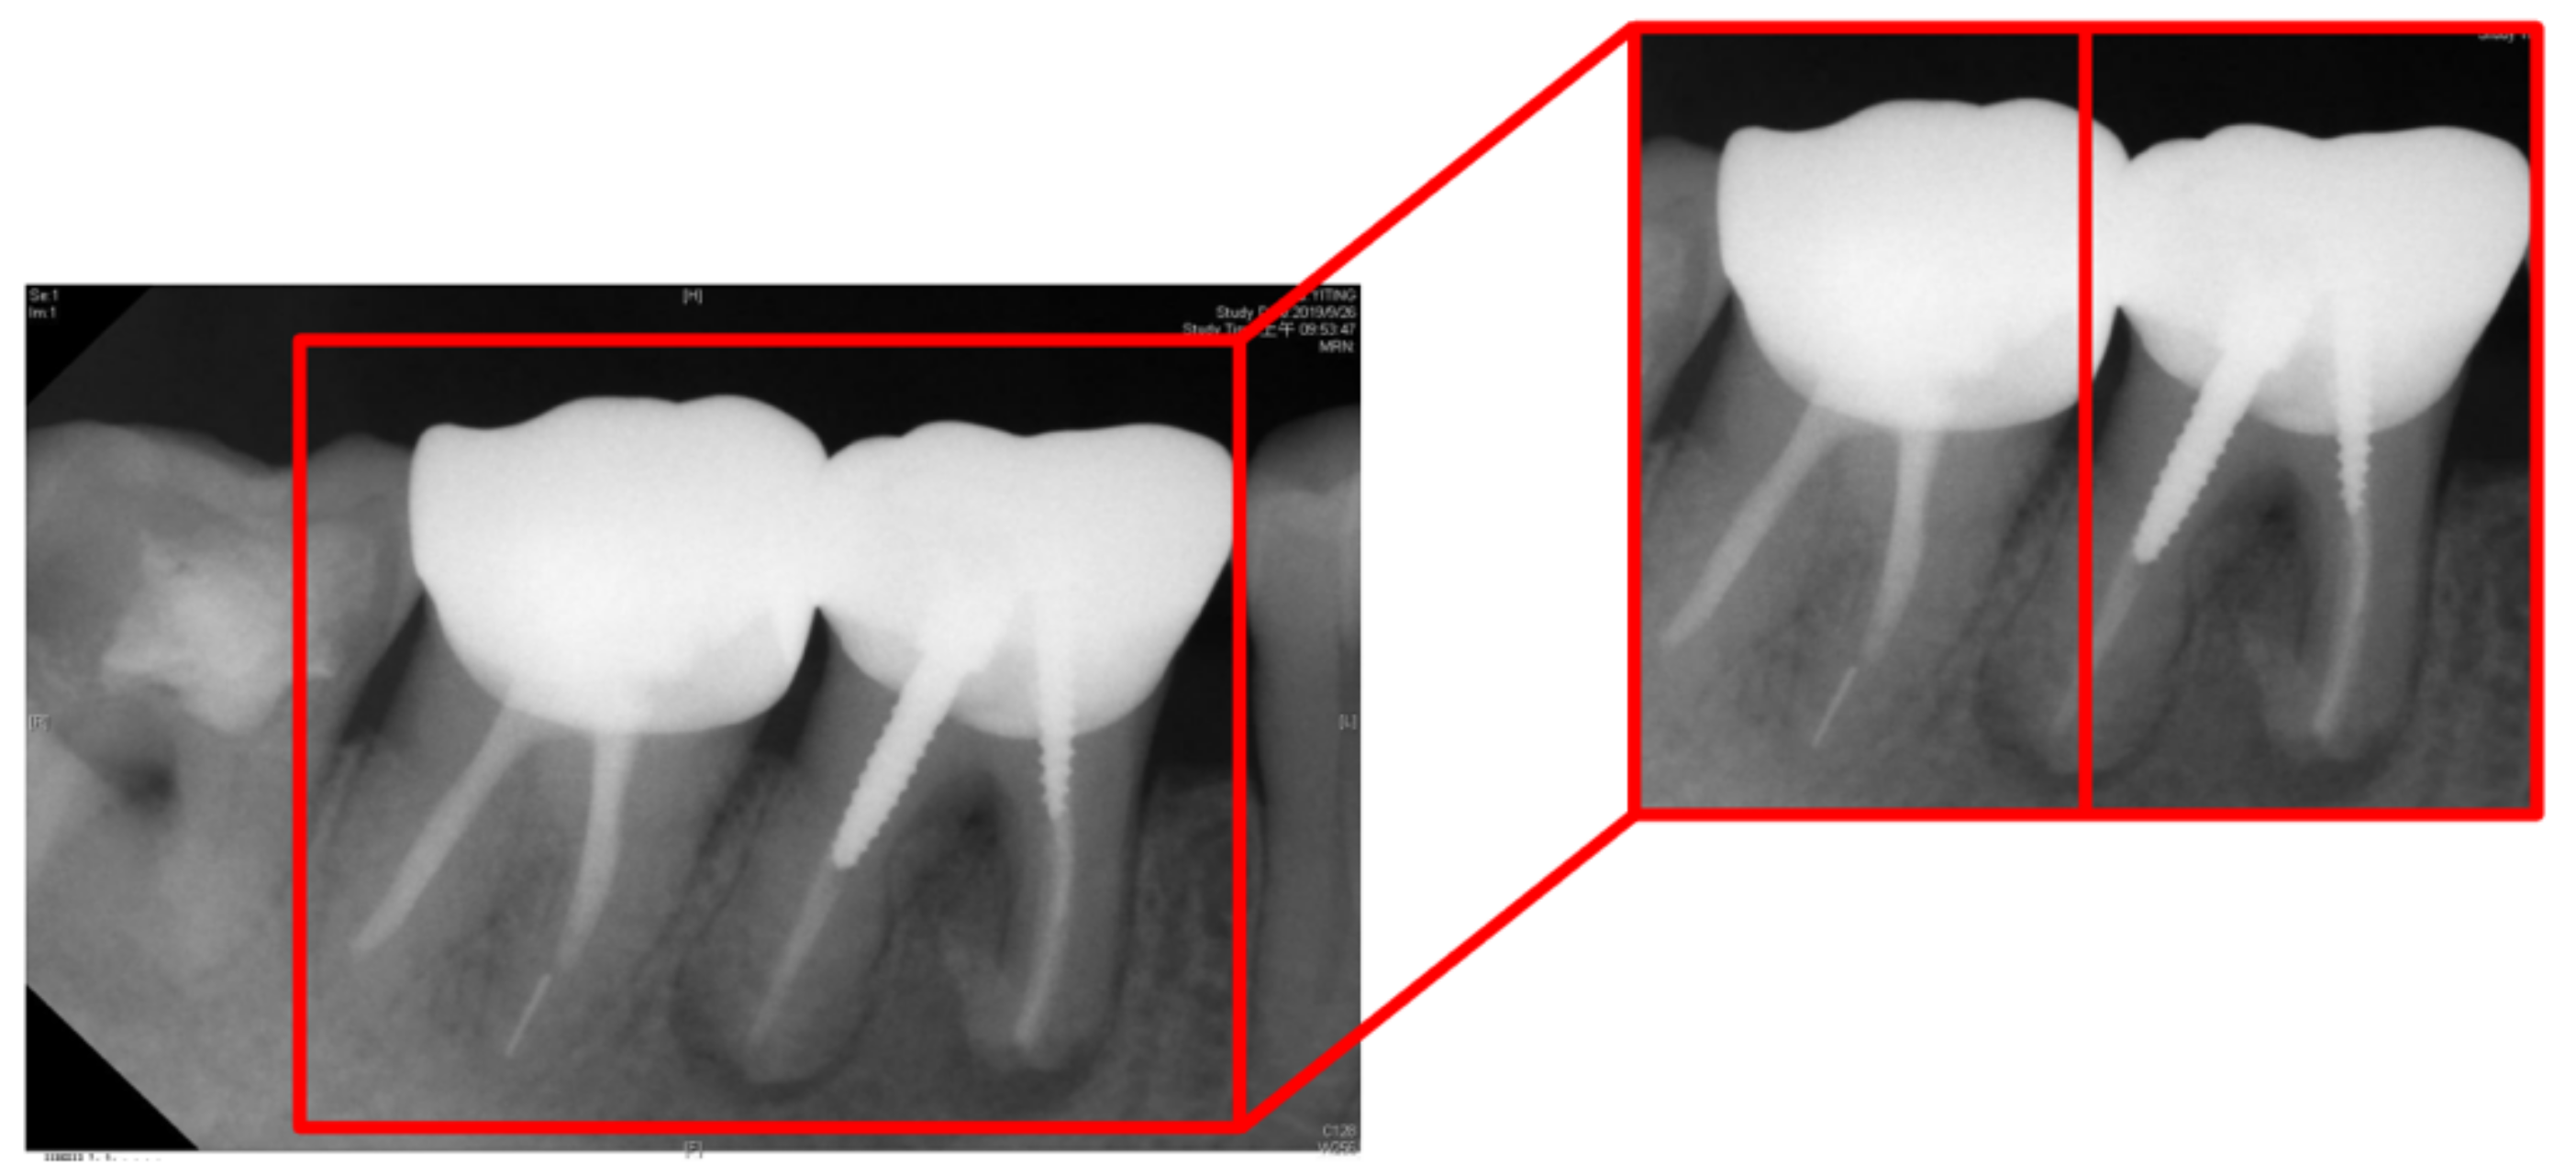

| Tooth Position in Figure 13 | Left | Right |

|---|---|---|

| Clinical Data | Normal | Lesion |

| This Work Before Enhancement | 90.91% Normal | 94.70% Lesion |

| This Work After Enhancement | 93.93% Normal | 97.35% Lesion |